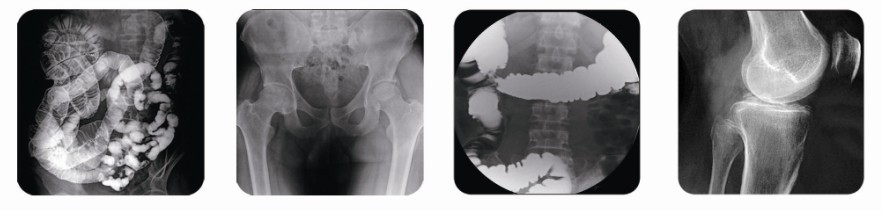

其實(shí),相對(duì)于胃腸X射線機(jī)這樣的醫(yī)療產(chǎn)品,進(jìn)口的自然是比國(guó)產(chǎn)要昂貴很多。現(xiàn)在,醫(yī)療科技的進(jìn)步已為我國(guó)醫(yī)療器械制造企業(yè)提供了較為廣闊的市場(chǎng)空間,我國(guó)醫(yī)療器械市場(chǎng)本土企業(yè)競(jìng)爭(zhēng)也是相對(duì)激烈的。從而也更加推動(dòng)國(guó)產(chǎn)醫(yī)療器械產(chǎn)品技術(shù)上的進(jìn)步。像普朗醫(yī)療的PLD6800胃腸X射線機(jī),創(chuàng)造性思維設(shè)計(jì),開啟了廣泛的臨床功能應(yīng)用,如胃腸透視/攝影,消化道檢查,胸部攝影,頭顱及全身骨骼攝影、胃腸造影、食道造影、脊髓造影、關(guān)節(jié)腔造影、膽道造影、支氣管造影、靜脈造影、周邊血管造影、泌尿系統(tǒng)造影、子宮輸卵管造影、兒科影像檢查、介入放射治療應(yīng)用等。另外,舒適方便,簡(jiǎn)約精巧的診斷床可直觀顯示的人機(jī)界面,采用全球領(lǐng)先的觸摸屏控制技術(shù),使人機(jī)對(duì)話更加直觀,方便,易懂;一體組合式操作手柄,可以輕松控制床體、影像系統(tǒng)和旋轉(zhuǎn)腳踏板的運(yùn)動(dòng)、點(diǎn)片。

(普朗醫(yī)療品牌——高頻數(shù)字化醫(yī)用診斷X射線機(jī)PLD6800(胃腸X射線機(jī)))